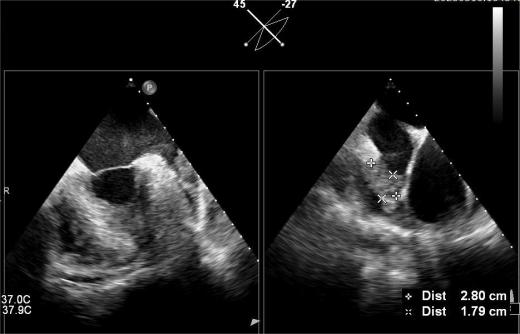

▲血栓位于心耳中段

其中首场公开演示的左心耳血栓封堵病例具有极高难度,患者术前TEE显示左心耳血栓形成伴机化,血栓位于心耳中段,近中端絮状物明显。封堵机会只有一次,选型和操作稍有失误,都会增加手术风险。因此手术采取全麻,并安装了抗栓塞脑动脉保护装置,以减少术中风险。通过TEE引导下测量左心耳大小以及确认左心耳血栓位置,李岳春教授凭借自身丰富经验最终决定使用LAmbre 2632型号,采用推送式植入法将左心耳血栓牢牢锁死于远端,并且封堵器一次成型,封堵效果极佳,结束后取出脑保护装置,均未见血栓,顺利完成了此台高难度的手术,获得了学员们的一致认可。